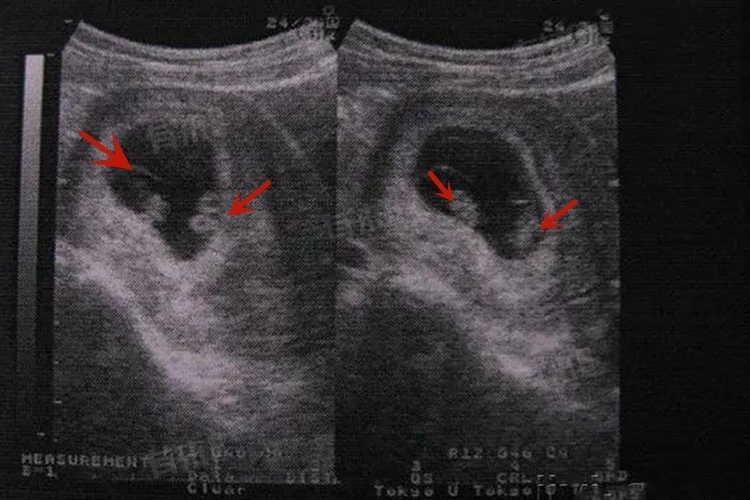

- 双胞胎妊娠的风险相对较高,所以产检次数要比单胎更为频繁。通常在孕早期确诊怀孕后,应每1-2周进行一次超声检查,密切监测胚胎发育情况、是否为双绒毛膜双羊膜囊或单绒毛膜双羊膜囊等胎盘胎膜情况。